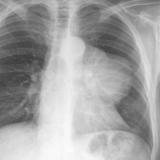

Case 8a Thymoma PA

Date: 03/27/2009

Views: 9449